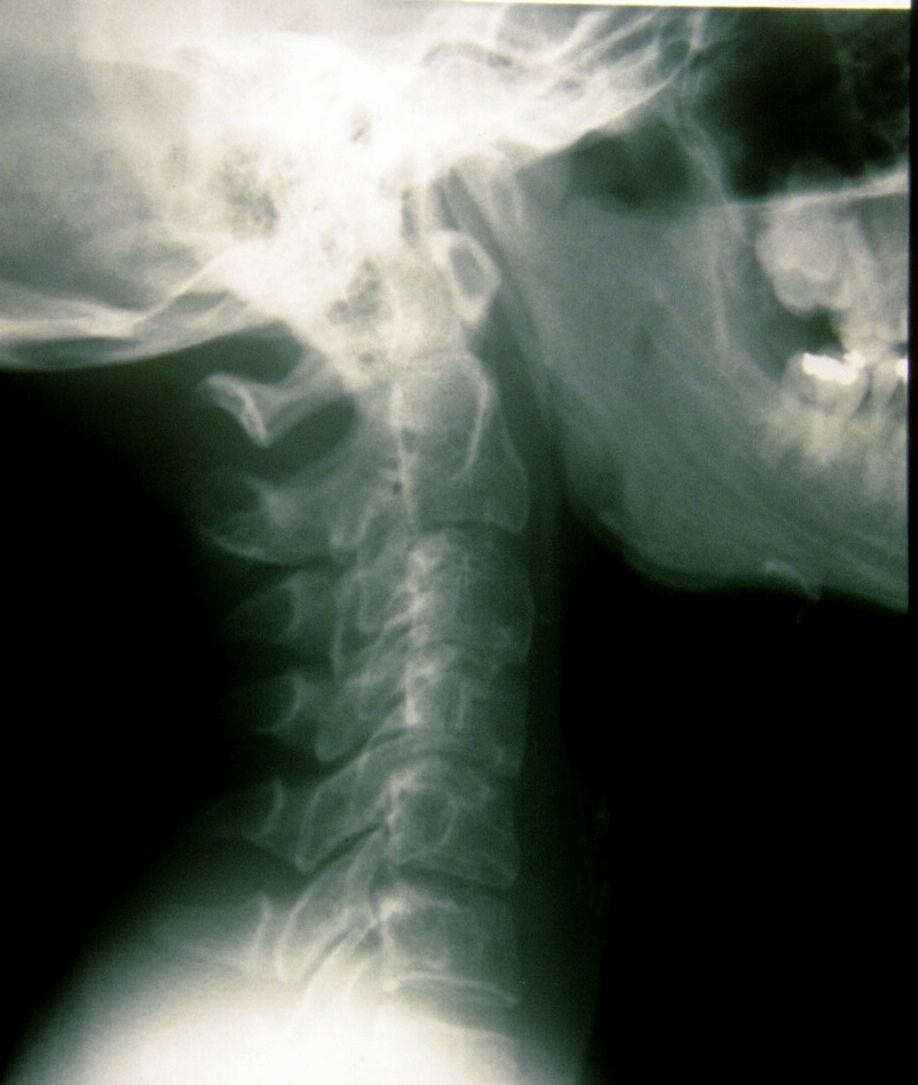

Seudoacondroplasia. [Pseudoachondroplasia]